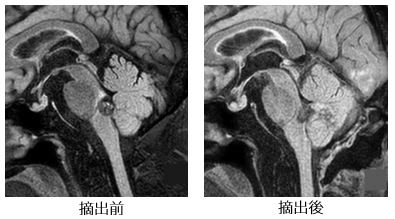

脳のさまざまな部位に発生する異常血管の塊です。出血を繰り返して脳の圧迫や刺激による神経症状(てんかん、麻痺、構語障害、嚥下障害、頭痛、めまい、複視など)の悪化を来たすことがありあす。出血を繰り返し神経症状が悪化する場合やてんかんの原因になっている場合には摘出術を行います。